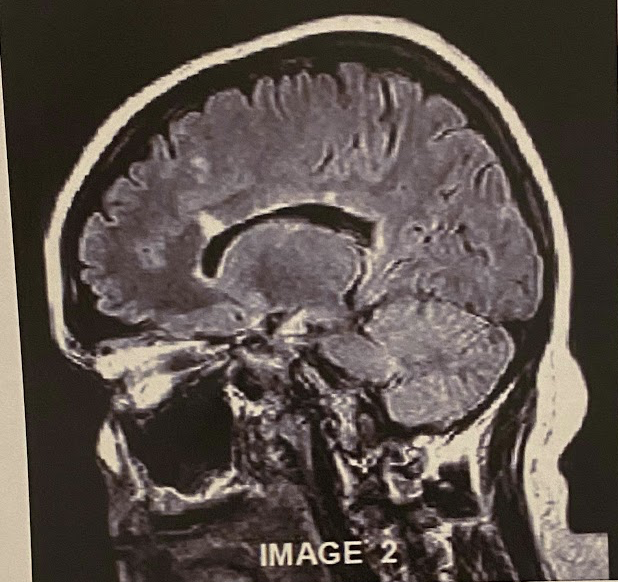

Q

The sagittal scan, demonstrates typical hyper intense tendril-like projections in the corpus callous characteristically seen in patients with what disease?

A) Tuberous Sclerosis

B) Multiple Calcified Nodules

C) Multiple Sclerosis

A

This image is non-contrasted. It was acquired using a _______ sequence

A) Proton Density

B) T1

C) FLAIR

D) GRE